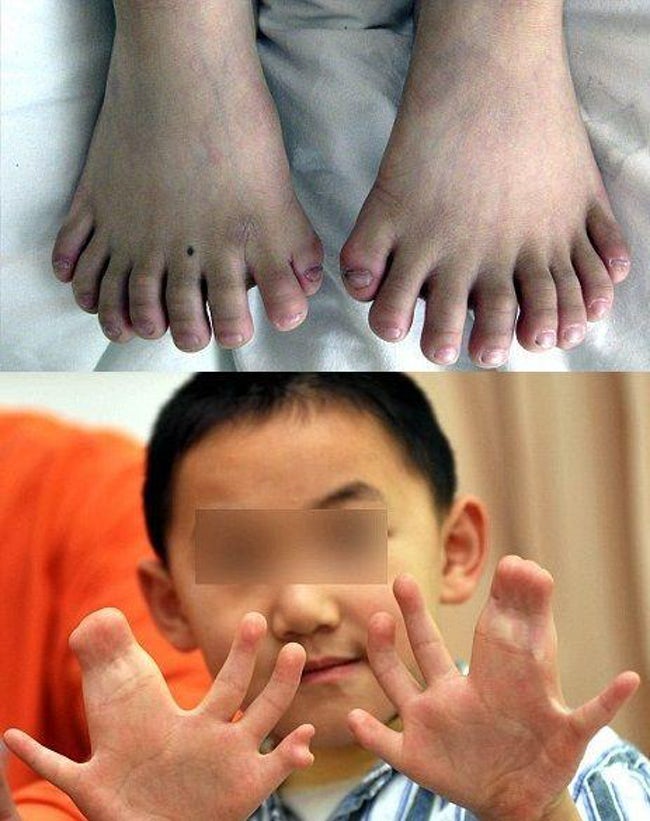

Կրկնակի մատներ

Կրկին չինացի այս փոքրիկի մոտ ձեռքերի վրա կա 15, իսկ ոտքերի վրա՝ 16 մատ։